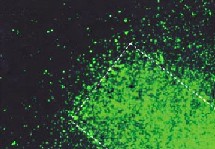

En un experimento reciente, Hofmann inyectó nanopartículas de hierro acopladas a un gen modificado que sintetizaba una proteína verde fluorescente en el interior de la articulación de una oveja.

Para colocarlo en el lugar deseado, utilizó un imán para mover el gen implantado por el interior del organismo. Las células de la oveja produjeron después proteínas verdes fluorescentes que resplandecían bajo la luz, lo que permitió observar el funcionamiento y comprobar el éxito de la prueba.